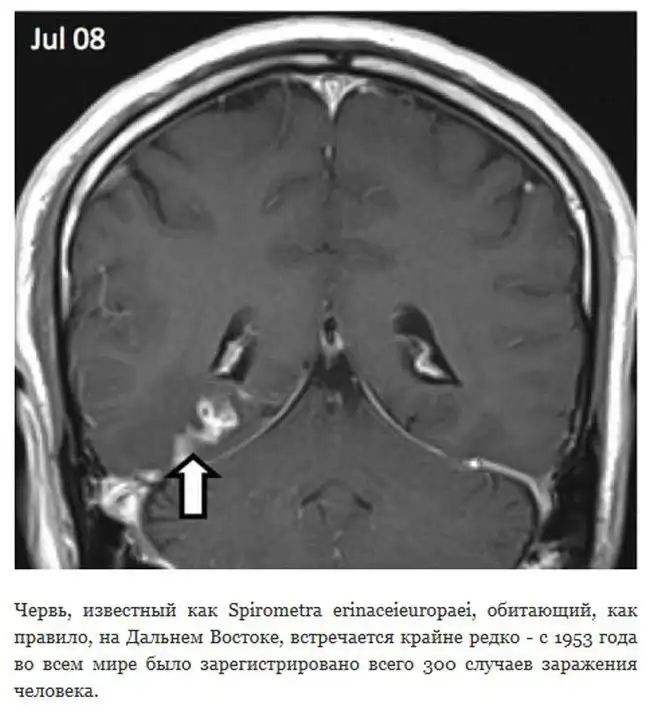

Паразитический червь 4 года блуждает по